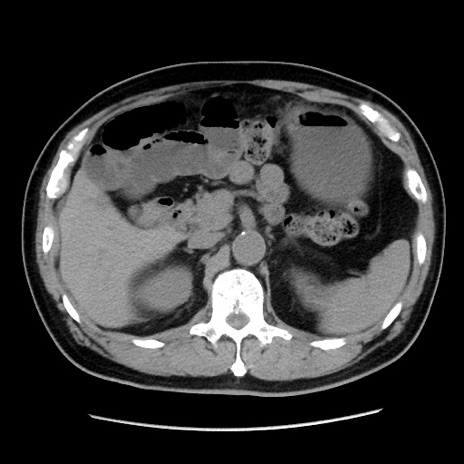

冠状断像